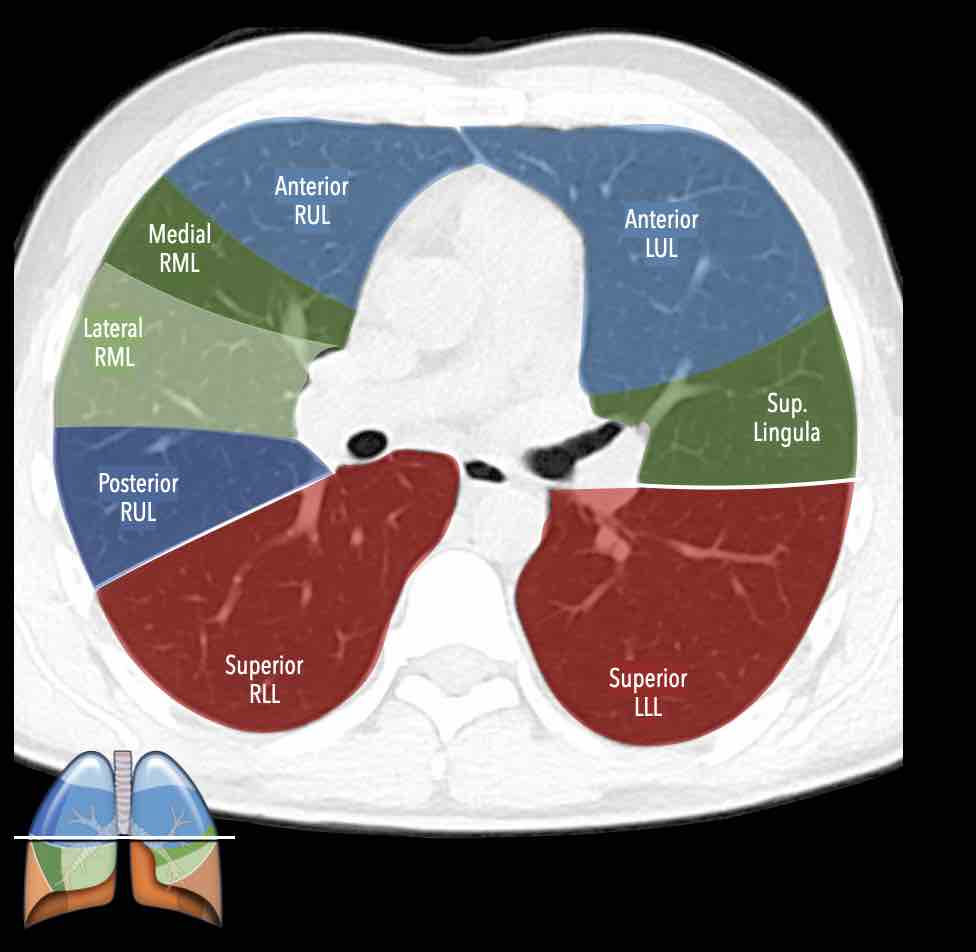

Các phân thùy phổi trên CT

Cuộn qua các hình ảnh để quan sát cách phổi được phân chia thành các phân thùy.